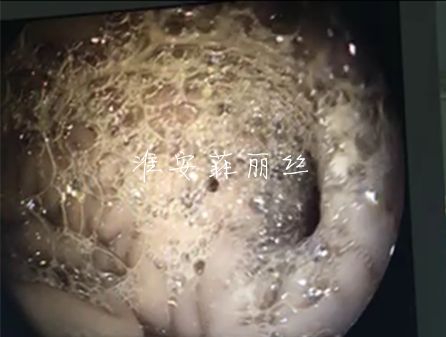

1、泰迪,美子,两岁,4.3kg,不明原因呕吐数日,宠物内窥镜(胃镜、食道镜)检查,诊断为胆汁返流性胃炎,胃、十二指肠红肿、溃疡。现已康复。

7、 淮安同行介绍转诊,一岁,比熊犬,食道异物,食道卡到骨头四天,内窥镜食道镜检查食道严重糜烂、溃疡、出血。内窥镜取出5公分的脊椎骨。

11、赛尼、斗牛、9月,8.0kg,几天呕吐,内窥镜检查:贲门和胃部出血性溃疡。